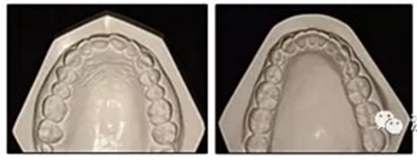

圖2. 治療前牙齒石膏模型

患者是一名39歲的白人婦女,病史不明。她主訴是她的右側(cè)顳下關(guān)節(jié)有不適癥狀,并希望改善她的笑容。她有一個對稱的臉型和一個II類2分類的微笑。她的側(cè)貌是凸的,90°的鼻唇角和骨性下頜骨發(fā)育不足??趦?nèi),上頜中線與面部重合,但下頜中線向右側(cè)偏移5mm;存在6mm的深覆蓋。她的兩側(cè)都是I類磨牙關(guān)系,左側(cè)是I類尖牙關(guān)系,右側(cè)是完全的II類尖牙關(guān)系。下頜右側(cè)第二前磨牙先天性缺失(圖1和圖2)。最初的全景片顯示了足夠的骨質(zhì)水平和全部的第三磨牙(圖3)。治療前的頭影測量片片和相應(yīng)的頭影測量圖(圖3)證實ANB為7°,Wits評估為6 mm的骨性II類錯合(表)。上頜切牙相對與面部和顱底的位置很好。下頜切牙前傾。診斷為II類2分類錯合畸形,伴有骨性下頜發(fā)育不足,右側(cè)顳下頜關(guān)節(jié)癥狀,下頜中線向右側(cè)偏移5mm,先天性右下第二前磨牙缺失。